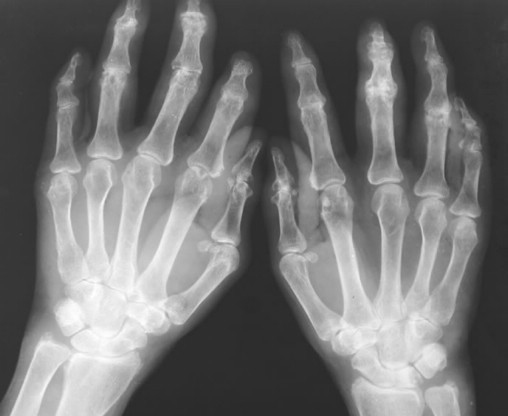

在骨科临床疾病当中,风湿病是比较常见的一种,对患者的危害大,治疗也比较困难。而且在近几年来,风湿病的发病人群也在不断的加大,给很多患者的生活都带来了影响。风湿病的治疗方法很多,中西医都有比较 的治疗这种疾病的方法,而中医一般采用针灸、推拿、药浴、中药等方法调整患者脏腑气血功能,增加人体抵抗力。下面就请郑州痛风风湿病医院专家来为大家简介中医治疗风湿病的几种方式,希望能够帮助风湿病患者们更快的 。